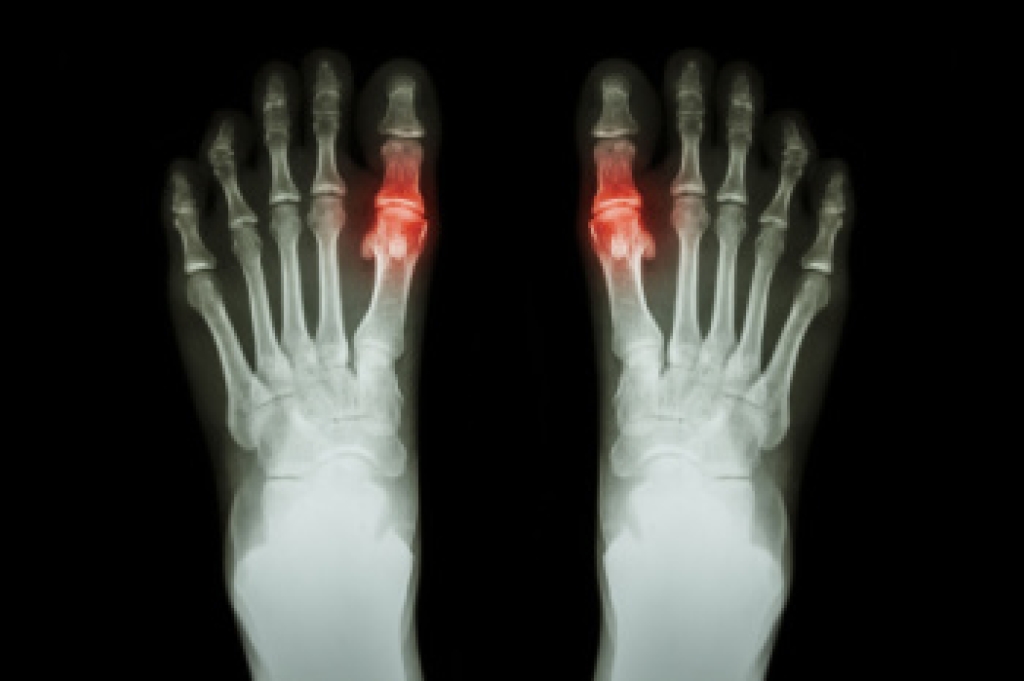

Gout is a form of inflammatory arthritis caused by the buildup of uric acid crystals in the joints, often affecting the big toe. This buildup, known as hyperuricemia, occurs when the body produces too much uric acid or fails to eliminate it efficiently. Common causes include a diet rich in purines, kidney dysfunction, or certain medications. Symptoms involve sudden and intense big toe joint pain, redness, swelling, and warmth. Diagnosis is made through blood tests, imaging, or joint fluid analysis. A podiatrist can help manage gout flares, recommend footwear modifications, and offer strategies to reduce pressure on affected joints. If you have had one or more gout attacks, it is suggested that you are under the care of a podiatrist who can help you to manage this painful condition.

Gout is a type of arthritis caused by a buildup of uric acid in the bloodstream. It often develops in the foot, especially the big toe area, although it can manifest in other parts of the body as well. Gout can make walking and standing very painful and is especially common in diabetics and the obese.

Gout can easily be identified by redness and inflammation of the big toe and the surrounding areas of the foot. Other symptoms include extreme fatigue, joint pain, and running high fevers. Sometimes corticosteroid drugs can be prescribed to treat gout, but the best way to combat this disease is to get more exercise and eat a better diet.